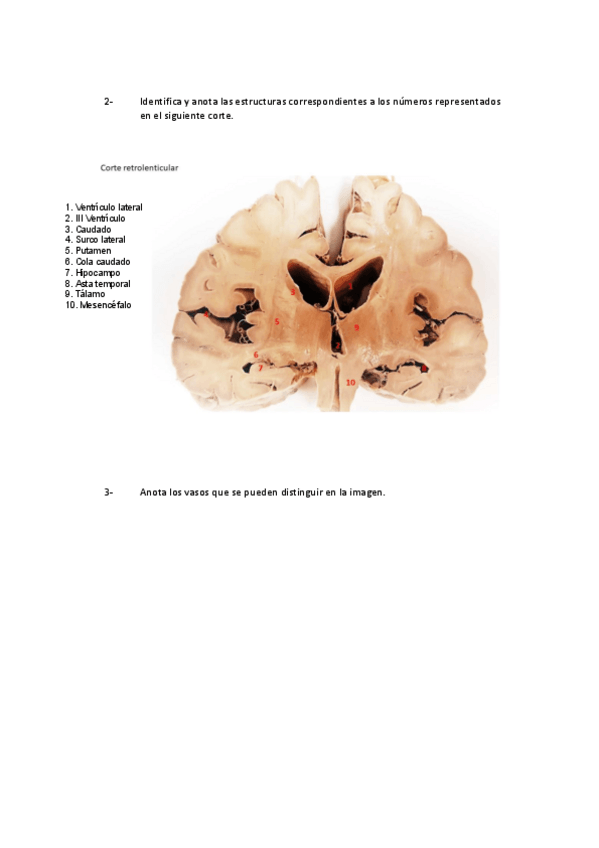

He publicado nuevos practicas de 2º Anatomía II: cabeza y sistema nervioso central: Guion-Taller-1.pdf

He publicado nuevos practicas de 2º Anatomía II: cabeza y sistema nervioso central: Guion-Taller-4.pdf